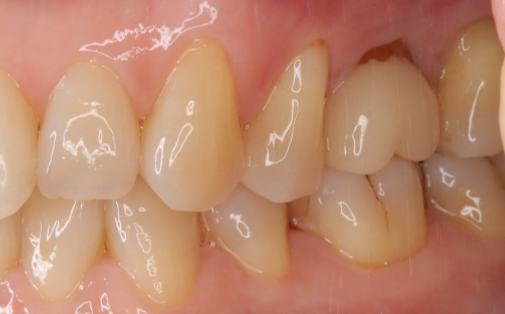

Before

After

左上の親知らずの歯を移植しました。20代前半の症例です。

ご自身の歯のため親和性が高く、移植後も不自由なく機能しています。